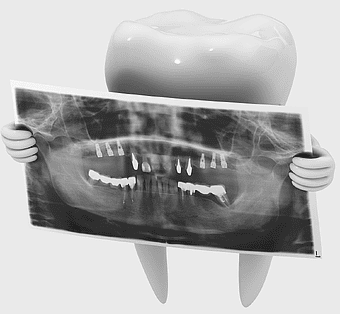

Dental X-ray film, tooth decay diagnosis, dental radiography, monochrome medical imaging, dental health visualization, x-ray tooth analysis, oral care imaging -

dental implant illustration, tooth pathology diagram, pediatric dentistry tools, oral hygiene equipment, dental care instruments, restorative dentistry visuals, dental surgery instruments -